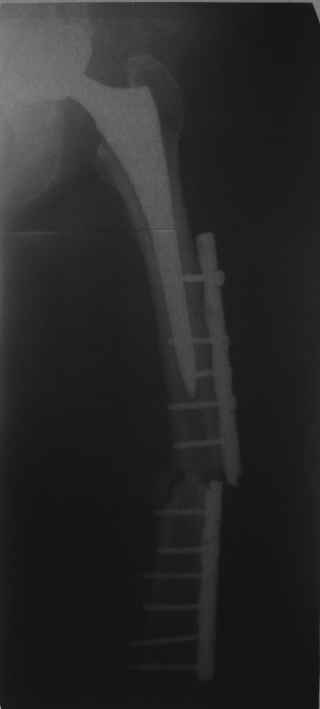

Это сплошной титановый стержень. На дистальном конце отверстия под кондуктор. На другом - канал под ножку глубиной 60 мм, стенки толщиной 2,5-3 мм. И там же продольный пропил, чтобы канал мог адаптироваться к ножке.

Обещанные ранее снимки Заранее спасибо.